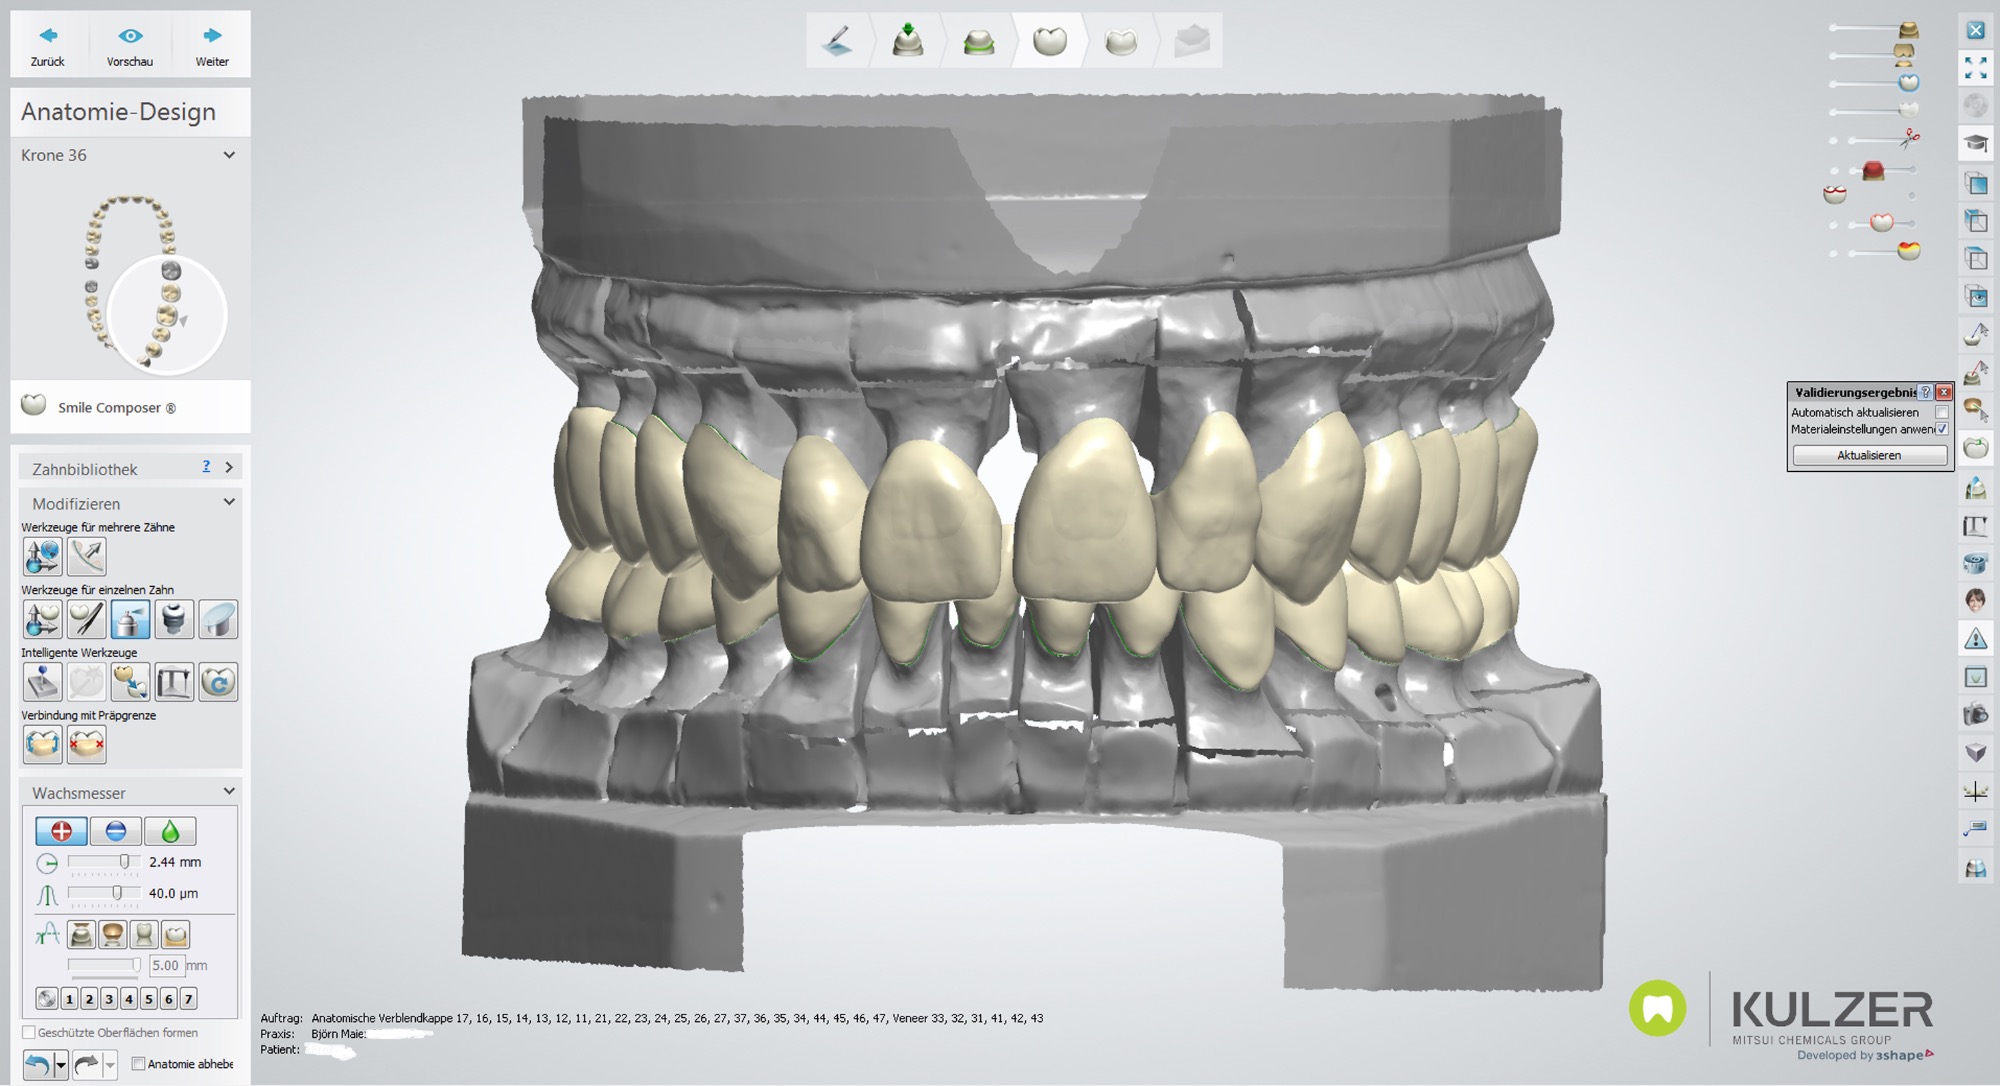

Teleskopierende Brücken im digitalen Ablauf hergestellt.